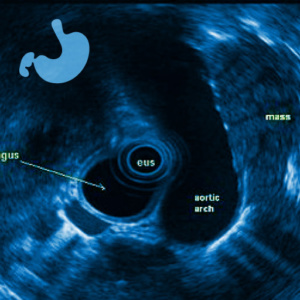

EUS, Gastromed